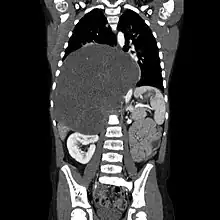

CT scan of a large ganglioneuroma within the chest cavity | |

Ganglioneuromas can be diagnosed visually by a CT scan, MRI scan, or an ultrasound of the head, abdomen, or pelvis. Blood and urine tests may be done to determine if the tumor is secreting hormones or other circulating chemicals. A biopsy of the tumor may be required to confirm the diagnosis.[4]